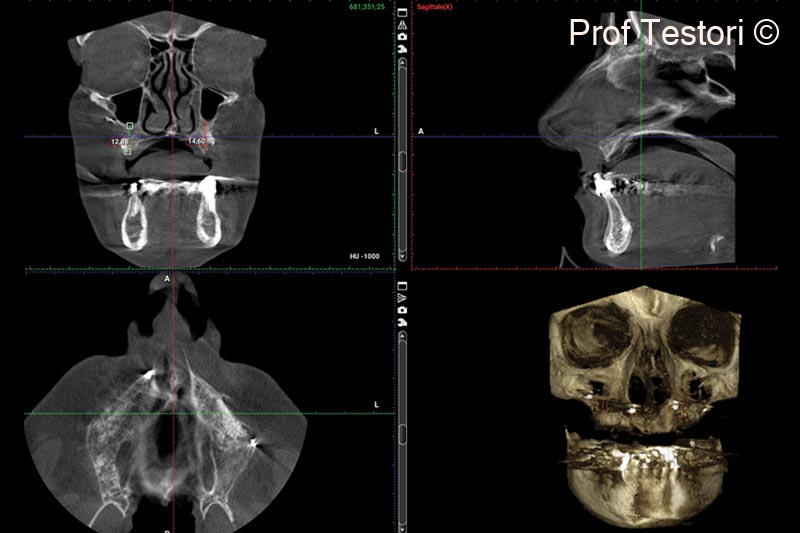

1. Pre-operative panorex and CBCT